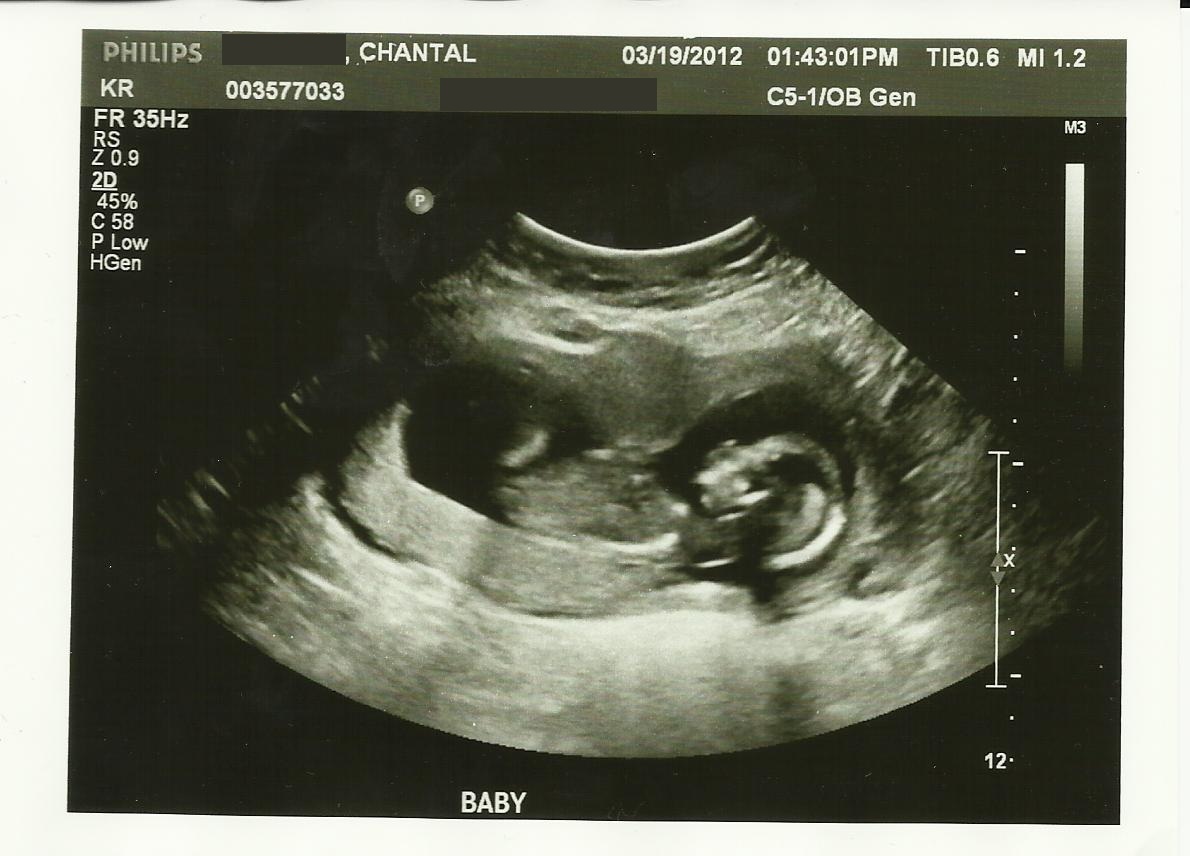

Skull guess please!

This is my ultrasound from 13 weeks 5 days. The tech did a quick crotch shot, but wouldn't look too hard. I am studing to be a Radiologist and I know that I for sure didn't see a nub.

Any guesses on the skull?? To me, the skull and chin look more female like, especially compared to my son's ultrasound photos!

Attachment 1763Attachment 1764Attachment 1765

I immediately thought GIRL when I saw your pics!

Thanks ladies! I am hoping for a girl this time! And I just have that feeling.